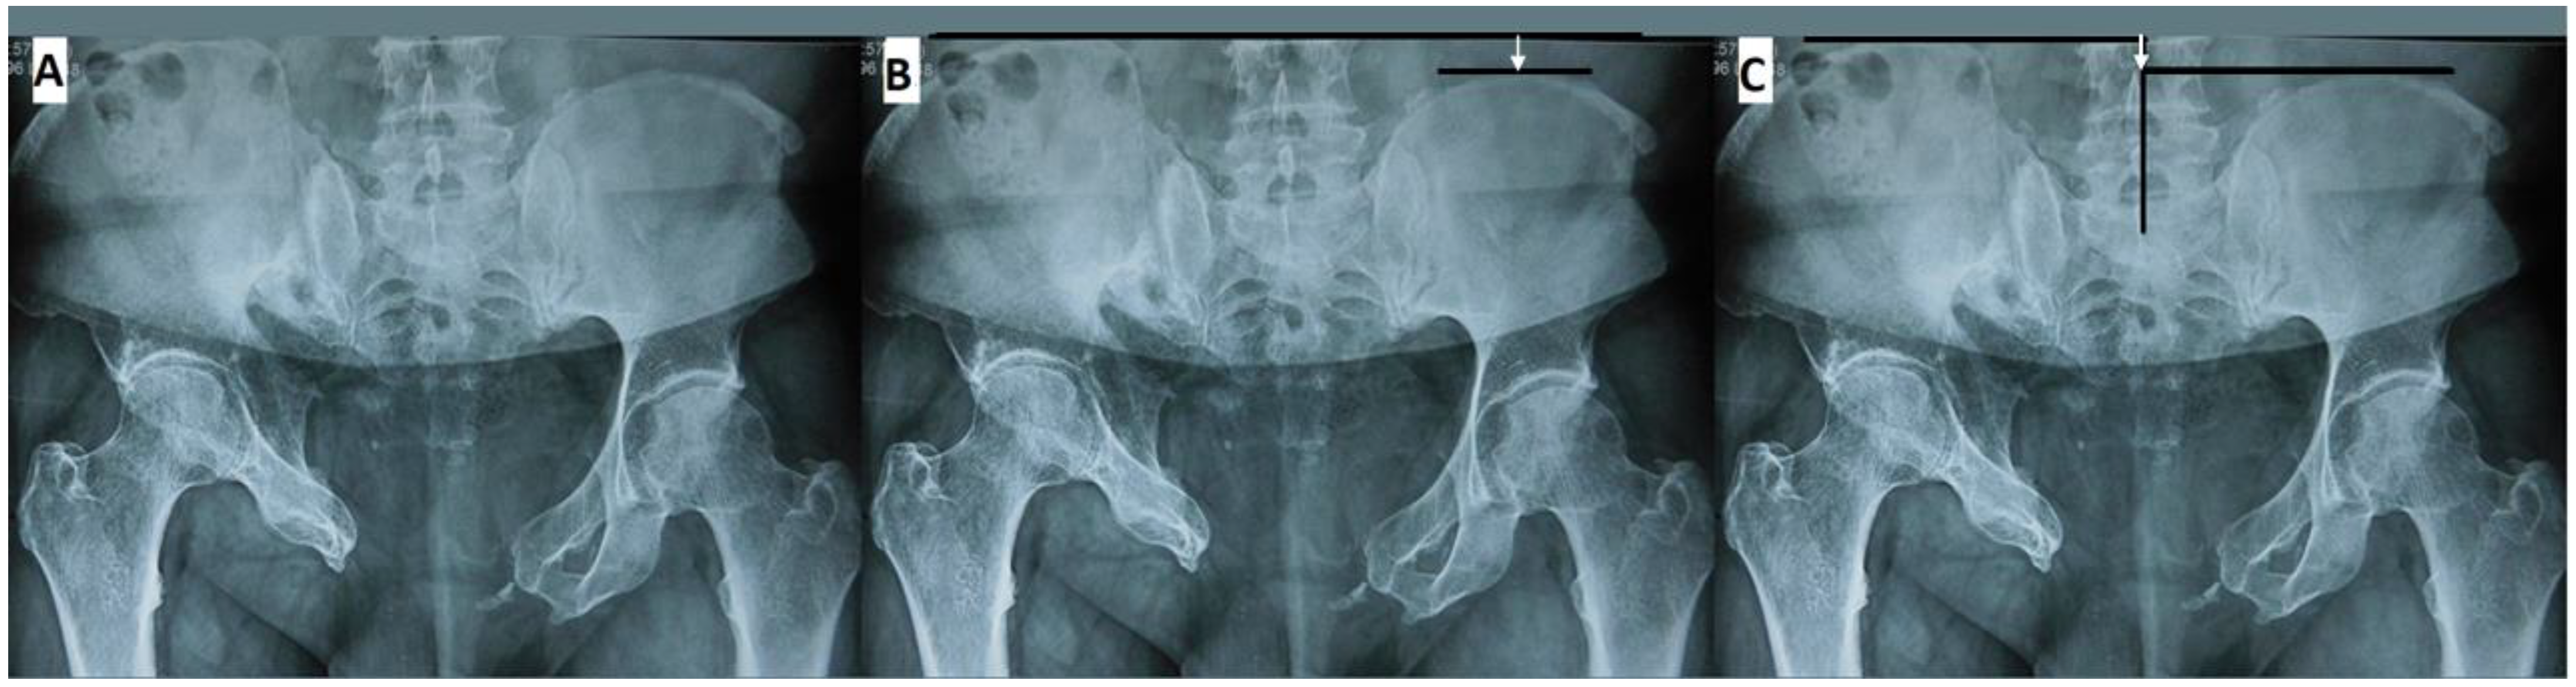

- Cano-Luís, P.; Giráldez-Sánchez, M.Á.; Andrés-Cano, P. Pelvic post-traumatic asymmetry: Assessment and sequenced treatment. EFORT Open Rev. 2018, 3, 335–346. [Google Scholar] [CrossRef]

- Herteleer, M.; Thüroff, J.; Rommens, P.M. Single stage reconstruction of a neglected open book pelvic injury with bladder herniation into the upper thigh: A case-report. Arch. Orthop. Trauma Surg. 2021, 141, 855–859, Correction in Arch. Orthop. Trauma Surg. 2021, 141, 1629. [Google Scholar] [CrossRef]

- Fang, C.; Alabdulrahman, H.; Pfeifer, R.; Tarkin, I.S.; Pape, H.-C. Late reconstruction of severe open-book deformities of the pelvis—Tips and tricks. Int. Orthop. 2017, 41, 1777–1784. [Google Scholar] [CrossRef] [PubMed]